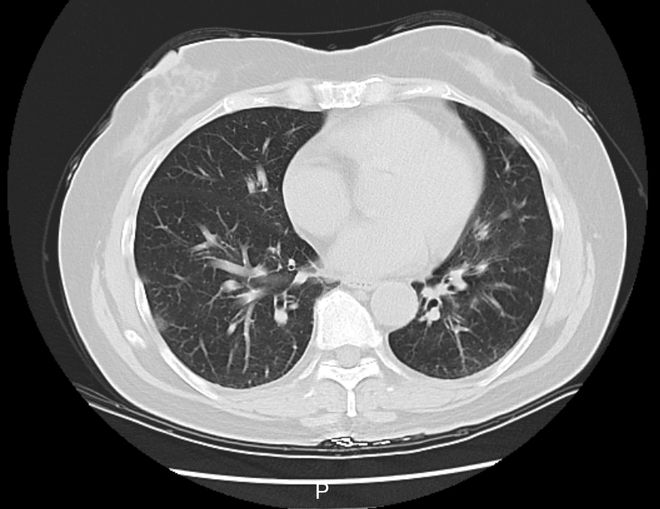

诊断肺部感染

诊断肺部感染需要结合患者的病史、症状、体格检查和实验室检查(如血常规、C反应蛋白)以及影像学检查(如X光、CT)等进行综合判断。